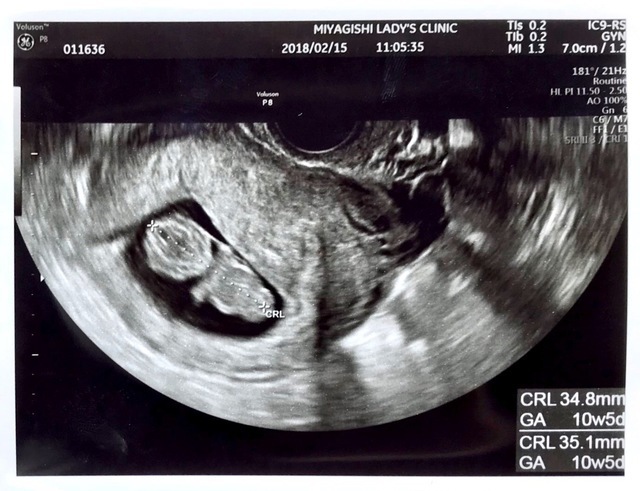

10週5日(10w5d・女の子)|さッちゃん さん(27歳)

エコー写真撮影時のエピソード:

妊娠して初めて人の形がわかったエコー写真です。 初めての妊娠で毎日不安でしたし、悪阻が酷く立っているのも大変でした。

このエコー写真をもらった時、やっとお腹にこの子がいるんだなって実感が湧いたと共にすごく愛おしく思いました。

この時の旦那は、父親になる実感がまだ無かったのが懐かしく感じます。 今の幸せがあるのは、この子のおかげだなって思いました。